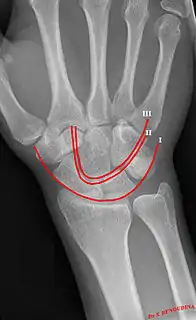

Gilula's lines are three arcs drawn on an AP radiograph of the wrist used to assess the alignment of the carpal bones.[1]

Gilula carpal arcs.

There should be no step-off in the contour of the lines when drawn on a normal wrist.

| First arc | running along the proximal convexity of the scaphoid, lunate and triquetrum |

| Second arc | running along the distal concavities of the scaphoid, lunate and triquetrum |

| Third arc | running along the proximal curvatures of the capitate and hamate |